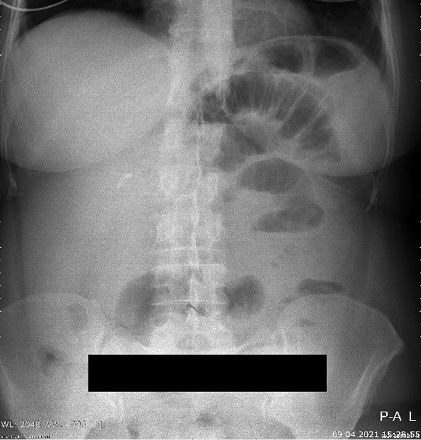

The patient was referred to a hematologist for proper staging and therapy. The positron emission tomography-computed tomography (PET/CT) scan showed a normal findings with low metabolic activity in the area of the wound infection (Figure 4). Bone marrow biopsy was negative. According to the Lugano score [7], the patient was diagnosed with Stage I of the disease.

Seven cycles of R-CHOP (rituximab, cyclophosphamide, doxorubicin, vincristine, and prednisolone) regimen were given to the patient as the first line of treatment. Post-chemotherapy PET/CT scan presented with normal findings. The patient is still in complete remission after the combined treatment with surgery and chemotherapy and regular future checkups are scheduled.

Figure 4. PET/CT scan with normal finding